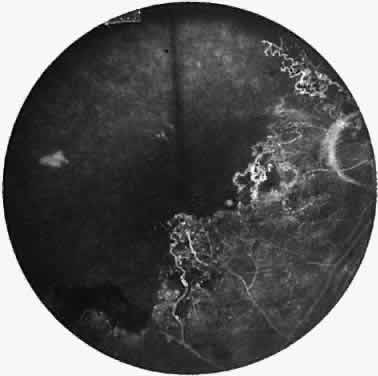

Signs of ocular inflammation are commonly encountered in Eales' disease, especially early in its course. Vascular sheathing is seen in most patients (Fig. 1). The degree of sheathing ranges from thin white lines on both sides of the blood column to thick heavy exudative sheathing. Areas of sheathing frequently leak dye with fluorescein angiography (Fig. 2). However, there is not a direct correlation between the regions of sheathing and staining.

Fig. 2. Fluorescein angiogram demonstrating abnormal vascular staining in a patient with Eales' disease. There was venous sheathing in these areas.

A varying degree of peripheral retinal nonperfusion is present in all patients with this disease. The nonperfusion generally is confluent and sharply demarcated from the posterior perfused retina (Fig. 3). Fine white lines representing the remains of obliterated large vessels (ghost vessels) often are seen in the area of nonperfusion. The temporal retina is most commonly affected.

Fig. 3. Fluorescein angiogram of the peripheral retina demonstrates the junction of normally perfused retinal vessels adjacent to an area of nonperfused retina. Notice the vascular abnormalities at the junction.

Elliot and Spitnas and colleagues have documented the abnormalities at the junction between the anteroperipheral nonperfused and the posterior perfused retina.9,10 Intraretinal hemorrhages often first appear in the affected area, followed by an increase in vascular tortuosity with frequent collateral formation around occluded vessels (see Fig. 3). Microaneurysms, arteriovenous shunts, and venous beading are commonly seen at the junction (Fig. 4). Fluorescein angiography enhances these abnormalities and often demonstrates staining at the stumps of obliterated vessels.